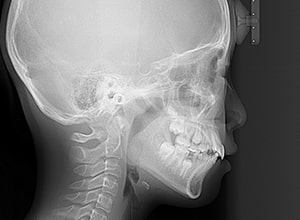

| 口腔内所見 | over jet 3.5mm,over bite4.0mm、下顎正中右側偏位2.0mm、大臼歯関係は左側Ⅰ級であったが、右下6は右下E早期喪失のため近心傾斜しておりⅢ級の臼歯関係となっていた。また上下顎前歯は軽度の叢生を呈していた。 |